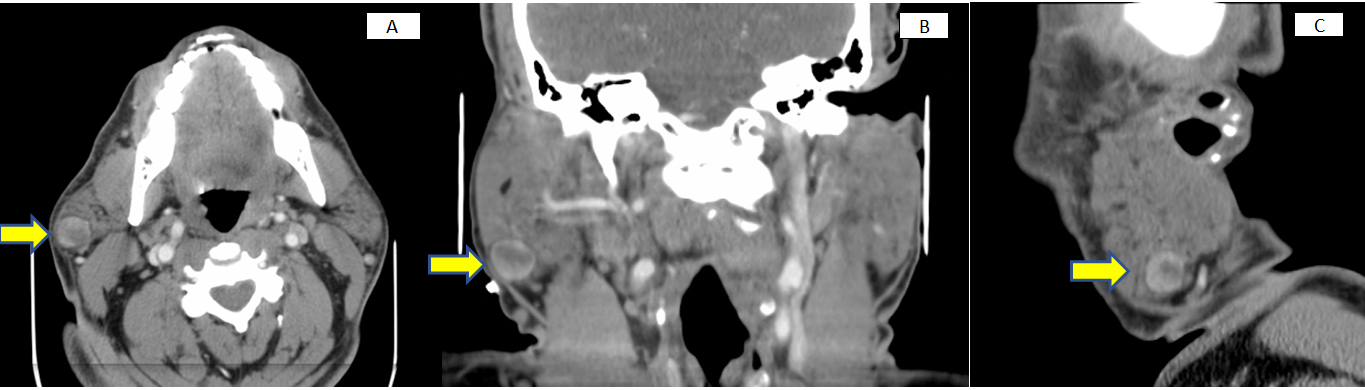

A 57-year-old male presented to the outpatient office with a chief complaint of a right parotid mass.  The mass was asymptomatic, had been present for 10 years, and had recently started enlarging. The patient was given a course of antibiotics by his primary care physician, with no change in size or quality of the mass. On exam, there was a 2cm well-defined, mobile mass in the right parotid gland, clinically within the parotid capsule.  A computed tomography (CT) scan of the soft tissues of the neck with contrast revealed a 1.7 cm well-circumscribed, enhancing nodule within the superficial lobe of the right parotid gland (Figure 1).  No other head and neck lesions or enlarged cervical lymph nodes were identified.

Figure 1 1.7cm right lower lobe parotid tumor seen on CT scan (A axial view, B coronal view, C sagittal view).